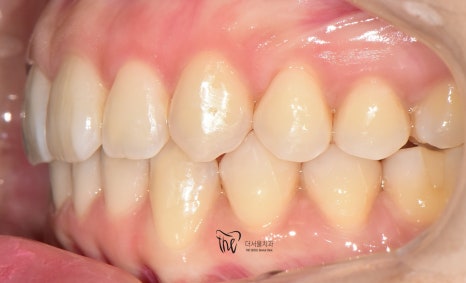

구강 내 사진을 먼저 보여드리면, 윗니가

아랫니를 깊게 물고 있어서 아랫니가 거의

눈에 띄지 않는 것을 보실 수 있습니다.

딱, 전형적 과개교합 의 양상을 보여주고 있습니다.

그러면서 치아의 중심선이 맞지 않으면서

악궁의 크기 또한 비대칭인것을 볼 수 있네요.